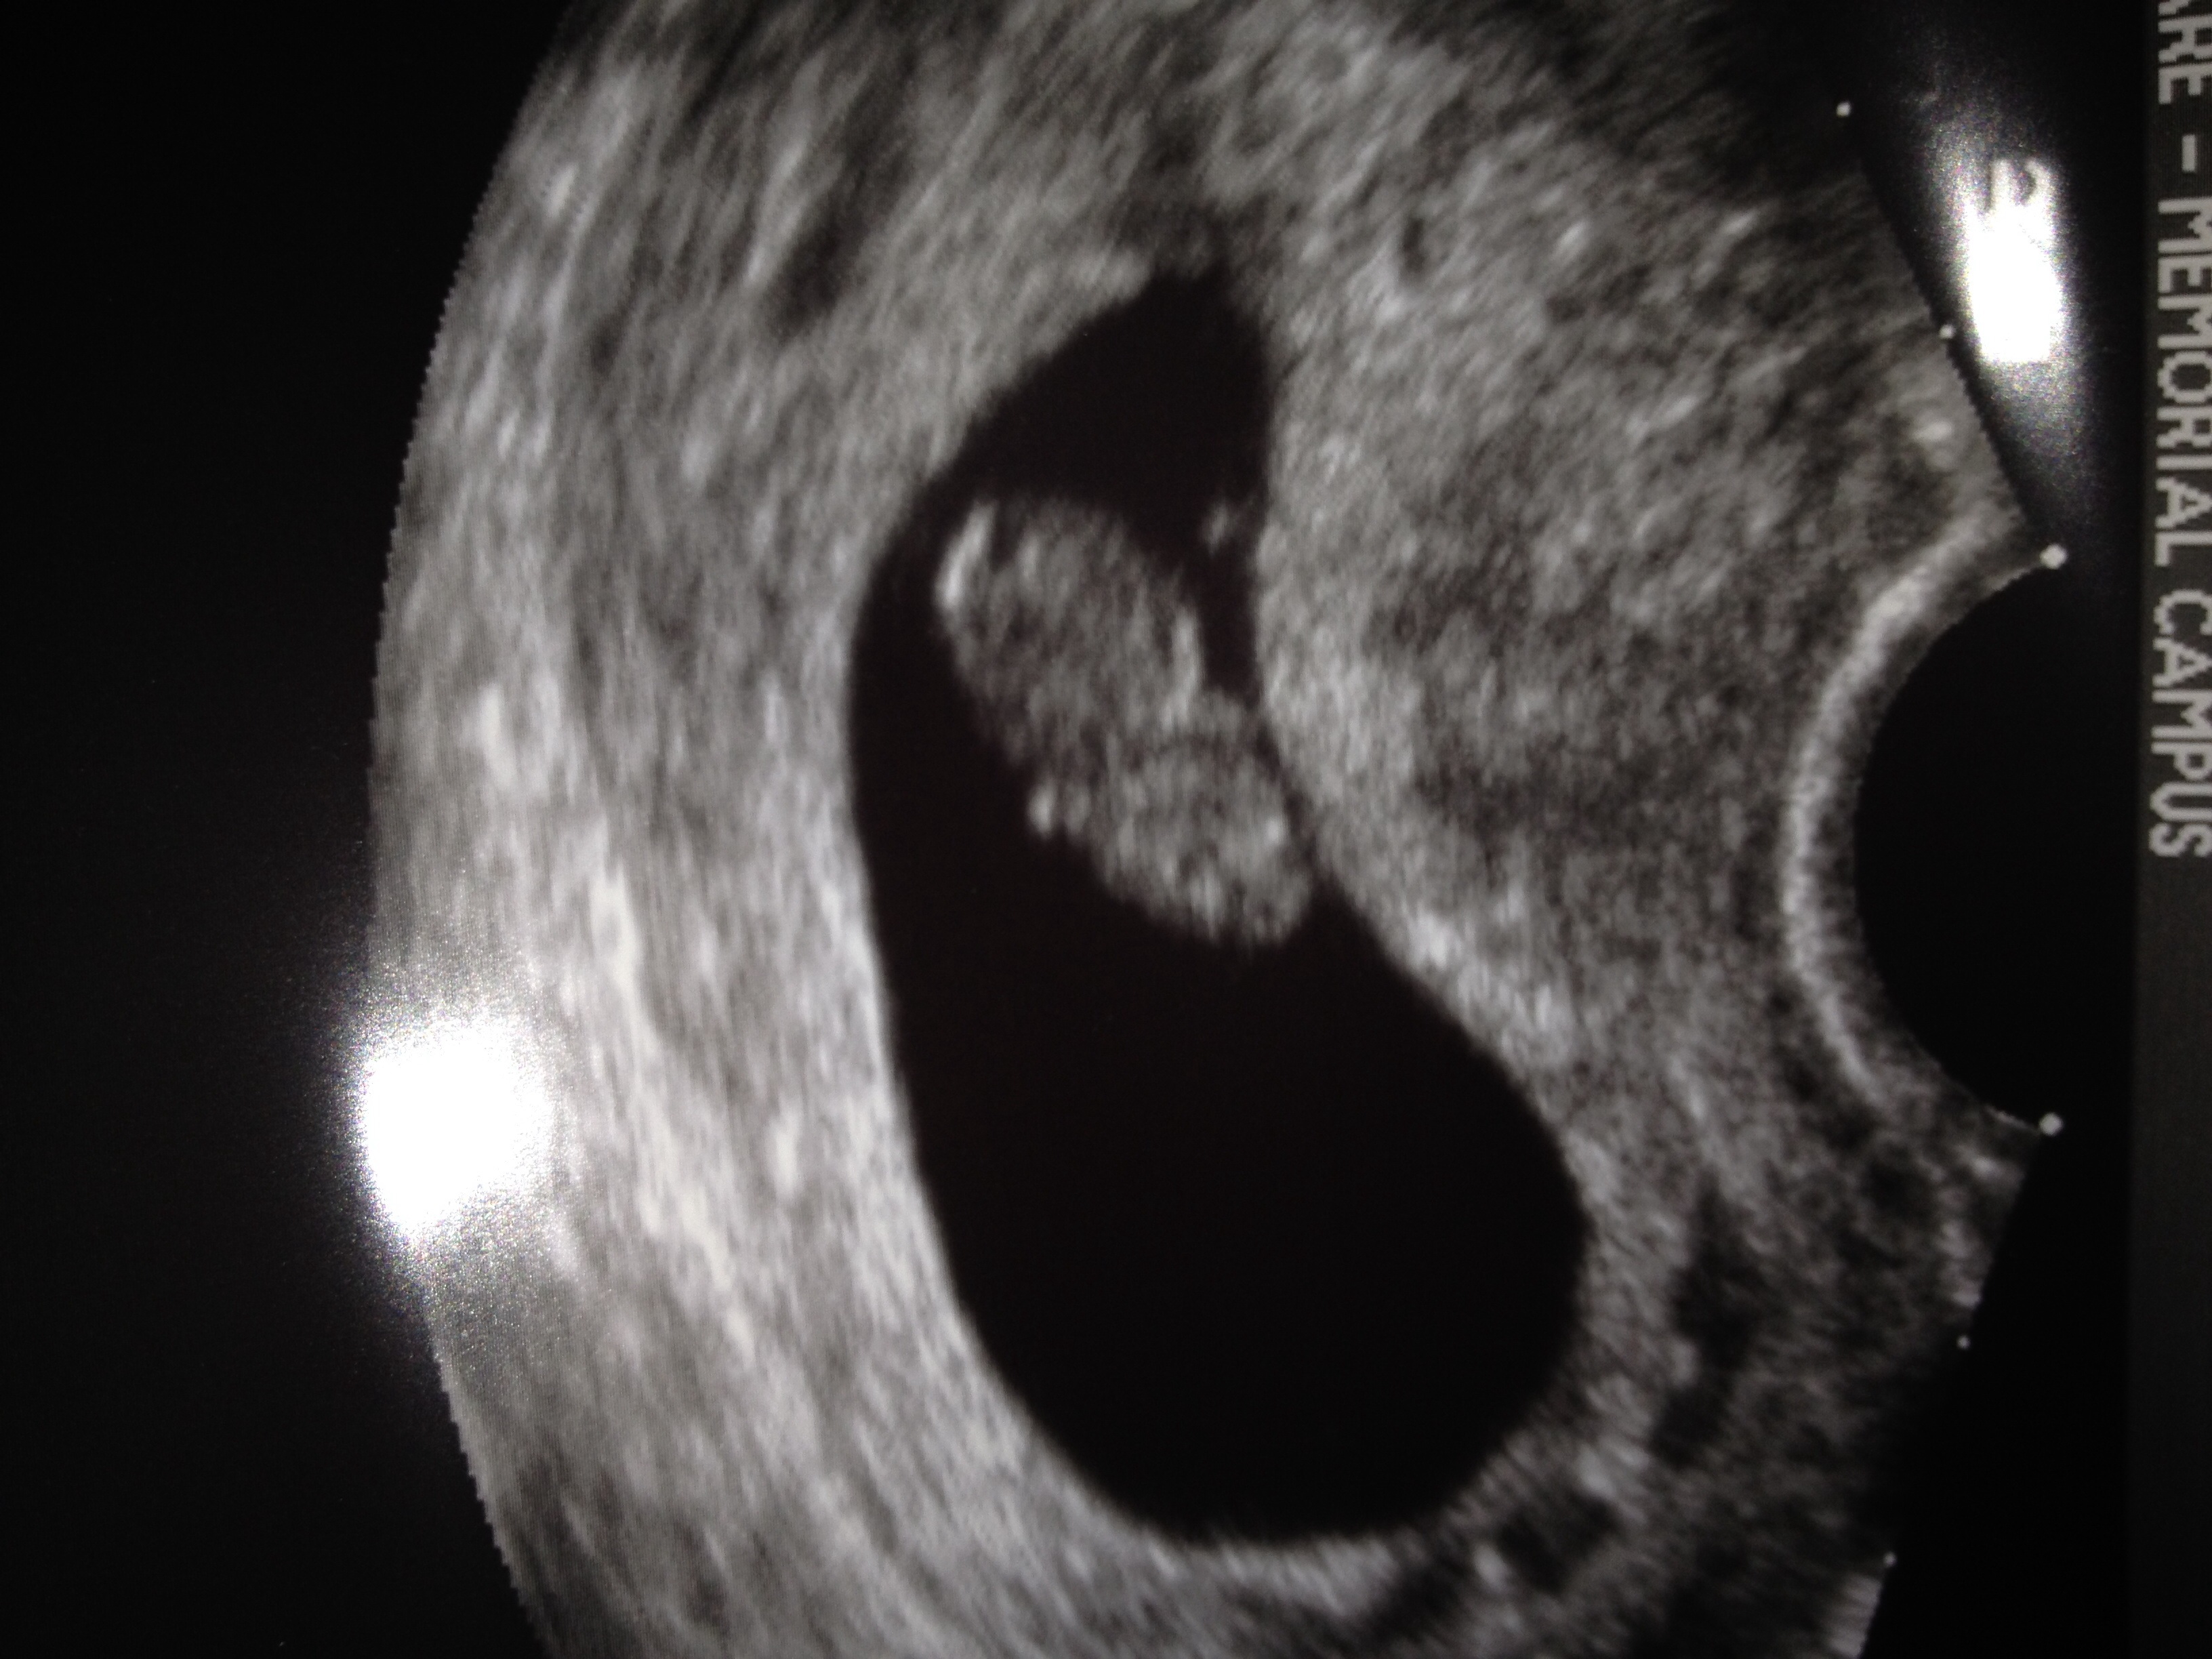

I did! It was confusing to say the least. We had a dating ultrasound and I'm 7w3d and we saw one baby that was up high in my uterus and another sac that was by my ovary that she couldn't see that well and said it was either another baby or a cyst. We had fraternal twins we lost when I was 19 weeks pregnant so twins aren't out of the question for us